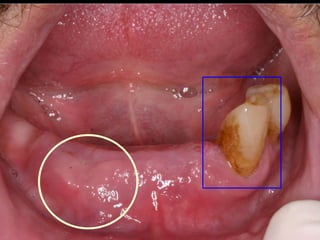

25 - L.C.S., sexo masculino, 18 anos de idade, se apresentou com queixa de aumento de volume na gengiva entre os dentes 23 e 24. Pelo exame clínico, constatamos a presença de um nódulo séssil, de contornos irregulares, coloração avermelhada, com sangramento abundante ao mínimo toque e evolução de 1 ano. O paciente apresentava higiene bucal precária com presença de placa bacteriana e tártaro. Com base no quadro clínico, o diagnóstico é: a) Fibroma e granuloma piogênico. b) Granuloma piogênico e hiperplasia fibrosa inflamatória. c) Lesão periférica (granuloma) de células gigantes e fibroma. d) Granuloma piogênico e lesão periférica (granuloma) de células gigantes. e) Hiperplasia fibrosa inflamatória e fibroma.

Granuloma Piogênico LesãoNodular Séssil ou pediculada Avermelhada ou vinhosa Sangramento espontâneo e áreas de micro-ulceração superficial

Granuloma Piogênico Lesõesnodulares de coloração avermelhada ou vinhosa Provavelmente uma reação inflamatória exagerada ao trauma menor Crescimento rápido, às vezes sangramento espontâneo Ocorre em qualquer idade mas parece mais freqüente em adultos jovens e adolescentes Localização mais comum: gengiva (NEVILLE,2001)

Granuloma Piogênico Lesõesmais antigas, são menos vasculares e mais fibrosas Papila interdental e regiões anteriores são áreas preferenciais, principalmente por vestibular (BORK,1996)

Granuloma Periférico deCélulas Gigantes Lesões nodulares de coloração avermelhada ou vinhosa Provavelmente uma reação inflamatória exagerada ao trauma menor Crescimento rápido, às vezes sangramento espontâneo Ocorre em qualquer idade mas parece mais freqüente em homens antes dos 16 anos de idade a após esta faixa torna-se duas vezes mais freqüente em mulheres Localização mais comum: gengiva

Granuloma (Lesão) Periféricode Células Gigantes A excisão cirúrgica deve ser antecedida de exame radiográfico, pois lesão não completamente removida e/ou com infiltração óssea, pode recorrer